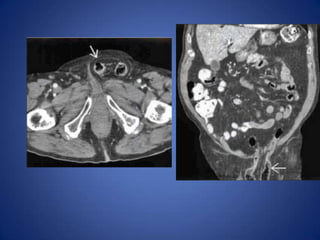

Urolithiasis

• Distal left ureteral stone may cause left lower

quadrant pain

• Diagnosis usually evident on CT

– Ureteral calculus, hydronephrosis, perinephric

stranding

Urolithiasis • Distal leftureteral stone may cause left lower quadrant pain • Diagnosis usually evident on CT – Ureteral calculus, hydronephrosis, perinephric stranding